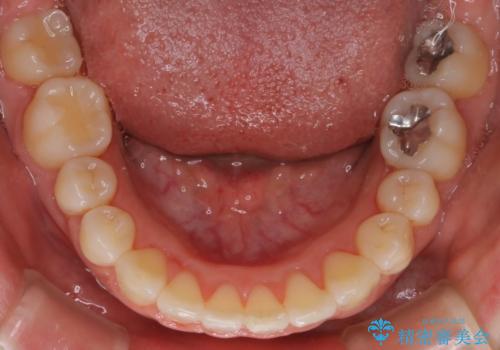

【審美装置】上下の前歯をきれいにしたい

- 矯正装置

- 審美装置

- 治療期間

- 1年8ヶ月

- 上下前歯のがたつきを主訴に来院されました。

口元も下げたいということもあり、上2本抜歯を行い治療を行いました。

抜歯を行い、前歯のがたつき、前歯の出ているところを改善できました。

患者様の満足感も高く治療を終えられました。